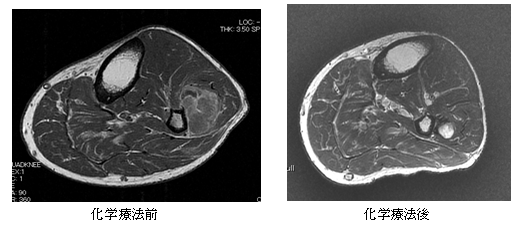

骨軟部悪性腫瘍の治療では化学療法の役割も重要です。手術前に腫瘍を縮小させるために用いたり、転移病変に対して使用します。特に近年、軟部悪性腫瘍に対しては新しい薬剤が複数使用できるようになったため、選択肢が広がっております。